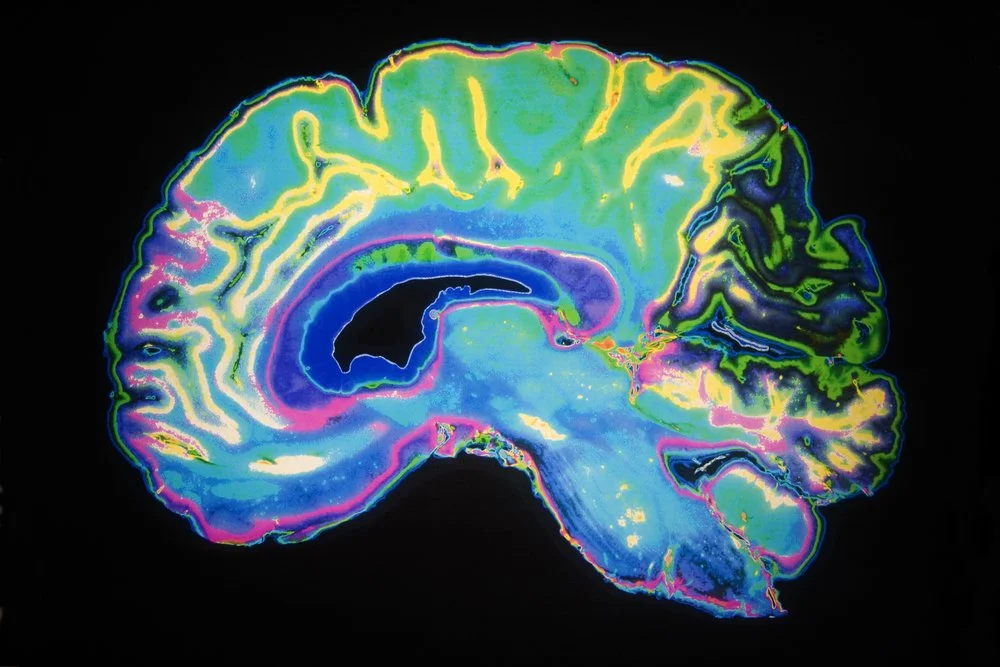

MRI of a human brain

In this interesting small study they took MRI’s of peoples brain activity while they were getting acupuncture at 3 different points. Ht 7, Kd 4, and St 36 The points are on the wrist, ankle and just below the knee. They found that different parts of the brain were modulated for each of the points. Some of the parts of the brain that were affected influenced emotional processing and pain-cognition pathways. These points have different functions in TCM so it’s cool that the MRI picked up different brain patters for each point too!